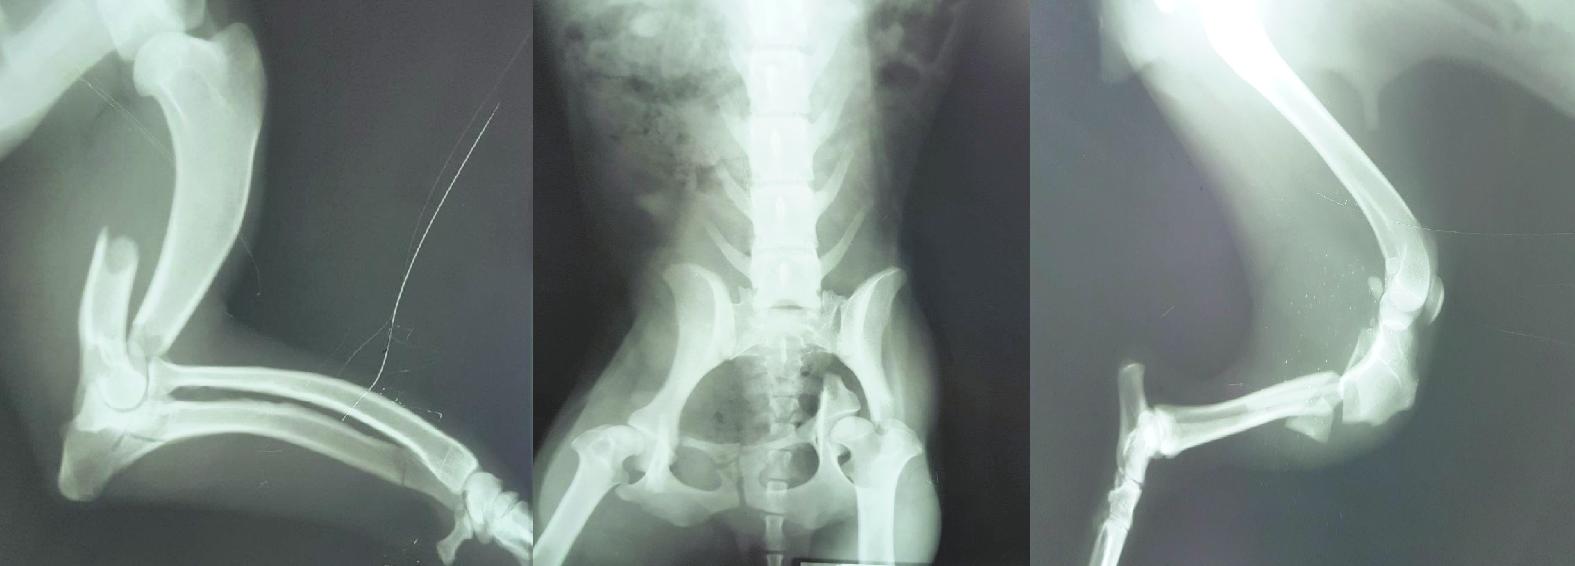

“Atendemos muchos perros politraumatizados. La mayoría son urgencias, como recientemente el caso de Canela, que fue atropellada. Tenía múltiples fracturas en sus patas traseras y delanteras. Vino de Cinco Saltos, rescatada por una señora. Había sido atendida por el colega Martín Gracejo, quien la estabilizó, derivó y llegó acá a tiempo acorde para realizar la operación”.